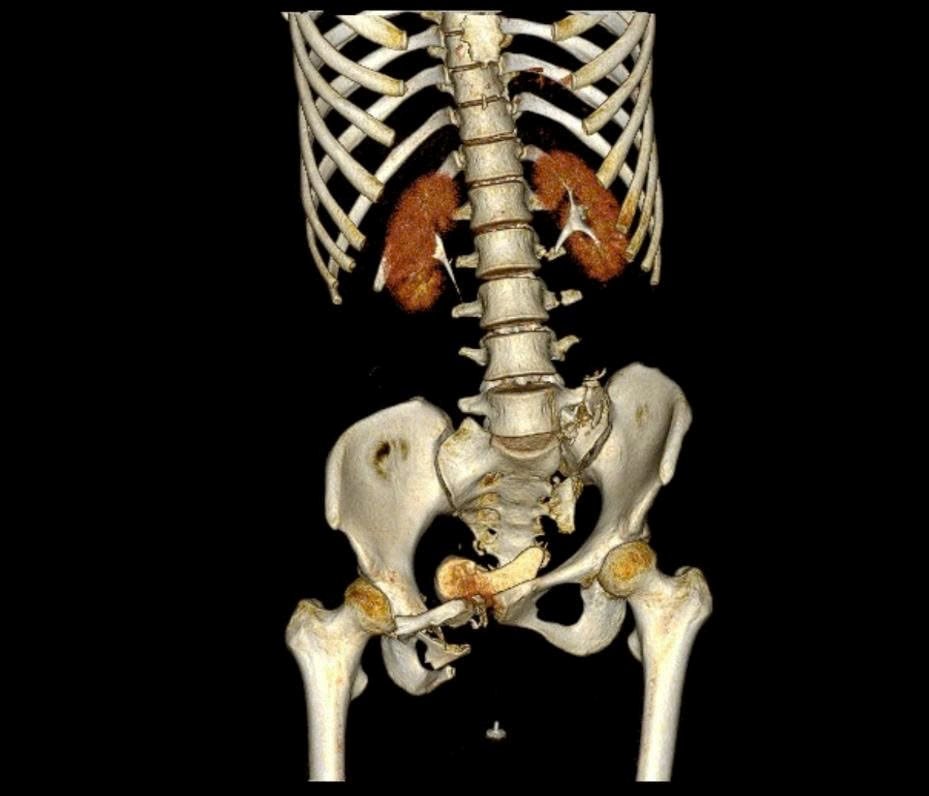

Bệnh nhân là N.T.H (24 tuổi, ngụ TP.HCM). Trước đó, vào khoảng 22 giờ ngày 13/9, chị H. bị xe container tông, được chuyển đến Bệnh viện Quân y 175 trong tình trạng sốc chấn thương/đa chấn thương nặng, gồm: Chấn thương ngực kín: dập phổi phải; Chấn thương bụng kín: vỡ bàng quang và buồng trứng phải, gây xuất huyết ổ bụng; Gãy gai ngang đốt sống L2–L5; Gãy phức tạp khung chậu kiểu “gió thổi”.

BS.CKI Trần Quang Khanh– Khoa Phẫu thuật chi dưới, Viện Chấn thương Chỉnh hình, Bệnh viện Quân y 175, một trong những bác sĩ trực tiếp tham gia phẫu thuật, cho biết: “Bệnh nhân bị gãy khung chậu kiểu ‘gió thổi’ (Windswept pelvic ring fracture) – một dạng gãy rất phức tạp, chiếm khoảng 6% các trường hợp gãy khung chậu.

Đây là loại gãy do chấn thương năng lượng cao, kết hợp giữa lực nén trước–sau và lực tác động bên, khiến một bên cánh chậu mở ra, bên còn lại khép lại, tạo hình ảnh đặc trưng như ‘bị gió thổi’. Thường tổn thương còn đi kèm gãy xương cùng và tổn thương khớp mu, làm mất vững toàn bộ vòng chậu, gây nguy hiểm tính mạng nếu không được xử trí đúng cách".

“Vì vậy, mục tiêu điều trị là phục hồi cấu trúc giải phẫu khung chậu và cố định vững chắc bằng nẹp vít, giúp bệnh nhân sớm vận động trở lại. Ở trường hợp này, khung chậu mất vững cả cung trước và sau, nên sau khi nắn chỉnh, chúng tôi cố định cung trước bằng nẹp vít và cung sau bằng vít xốp”. – Bác sĩ Khanh chia sẻ.